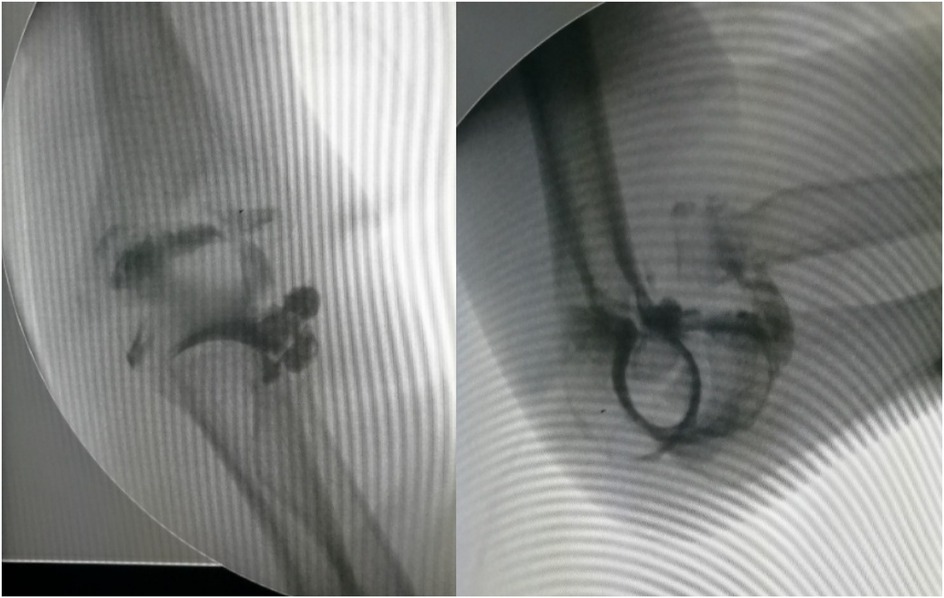

Objective: To investigate and analyze the application value of elbow arthrography in the treatment of chronic radial head dislocation in children. Methods: From January 2014 to January 2017, 15 children with chronic anterior radial head dislocation were treated (11 boys, 4 girls; average age 9 years, range 3-11 years). Intraoperative elbow arthrography was performed to assess the position of the radial head relative to the joint capsule. The nature of the dislocation was confirmed by opening the joint capsule to directly observe the relationship between the radial head and capitellum, as well as the morphology of the radial head. Reduction of the radial head was achieved via proximal ulnar osteotomy, and fixation was performed using a plate and screws with or without Kirschner wires (K-wires). Results: Elbow arthrography showed the radial head was located within the joint capsule in 12 cases and outside the capsule in 3 cases. Among the cases: All 8 congenital dislocations had the radial head within the joint capsule. Of the 7 traumatic dislocations, 4 had the radial head within the capsule and 3 outside. Direct inspection after capsulotomy confirmed the arthrography findings and revealed characteristic morphological differences. In congenital dislocations, there was no scar tissue between the radial head and capitellum, and the radial head fovea was shallow and flat. In traumatic dislocations, obvious scar tissue was present between the radial head and capitellum, and the radial head fovea was distinct. Follow-up ranged from 9 months to 4 years (average 2 years 5 months). Postoperative radiographs showed no cases of radial head re-dislocation or subluxation. Postoperative elbow range of motion improved in all patients, with no reports of pain or functional instability. Conclusion: Elbow arthrography serves as a valuable adjunct for differentiating between congenital and traumatic radial head dislocations, thereby informing both surgical strategy and the decision for supplemental fixation. When stable bony alignment is achieved, proximal ulnar osteotomy without annular ligament reconstruction represents an effective management strategy for chronic radial head dislocation in children.